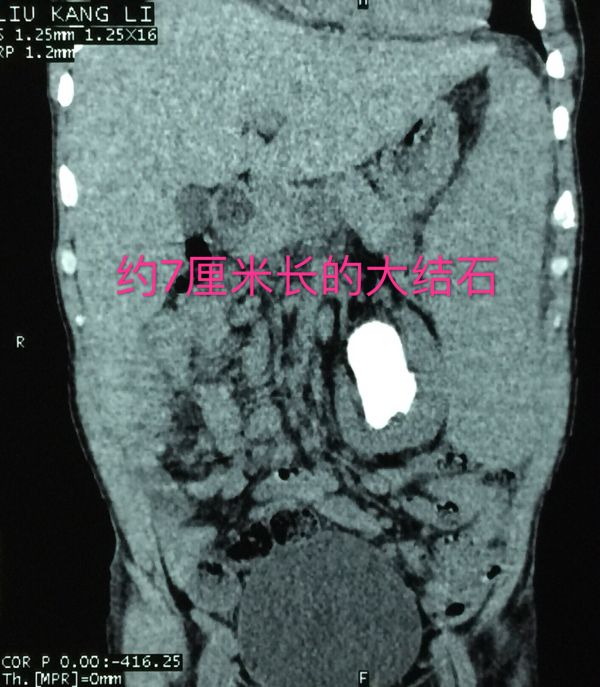

复杂性巨大肾结石

老刘白细胞149.59×10^9/L,右侧中上腹部有畸胎瘤占位,左肾结石非常巨大且复杂,而左肾又被白血病形成的巨大脾脏紧密包绕,还不包括胸膜和里三层外三层的肠道,从老刘的左肾取出结石无异于伸手从火红的熔铁炉内取出石头!要在老刘的身上做手术,将有80%的危险性,若不积极治疗,病人将面临100%的危险!

在老刘住院期间,泌尿外科的医生和护士众志成城,细心监护,一共请血液科、肿瘤科等科室专家进行了16次会诊,为他进行15次输血,2次抢救……虽然过程艰辛且曲折,但最终,泌尿外科的医护人员和老刘一起战胜了病魔,获得了成功,术后的老刘精神状态变得很好,白细胞值接近正常值,术后复查X光片显示结石被清理得很干净!12月10日,老刘顺利康复出院。出院当天,老刘一家还执意要和梁泰生主任合影留念以表感谢。

结石已被清理干净